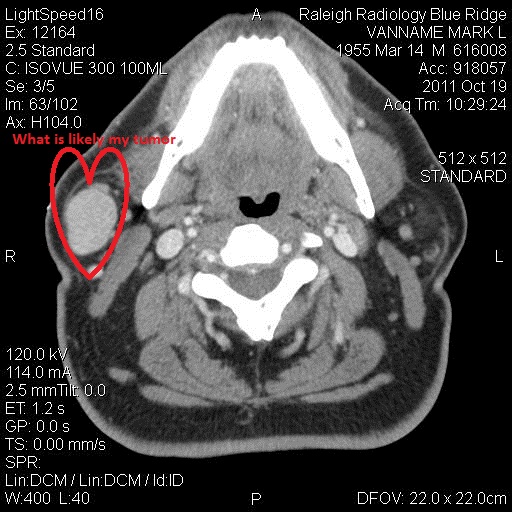

For this reason, administration of contrast material is helpful because cysts usually enhance on their periphery, whereas pleomorphic adenomas enhance solidly (Figs 3c, 7b).Now, with a little annotation of my own, here's a picture of the mass in my parotid gland.

Yes, ladies and gentlemen, I believe we have a tumor. I stress that word "believe" because, of course, everything I've just done is a bit of a mug's game. I have no training. I am self-diagnosing using an image I'm not even supposed to have seen. I've read multiple studies about how bad people are at self-diagnosing using Web techniques; I've heard figures of over 90% of the people being wrong, and almost everyone tending to choose a bad outcome.

That said, I think I'm right, and I'm now turning my energies to two things: hoping the tumor is benign, and investigating all my surgical options.